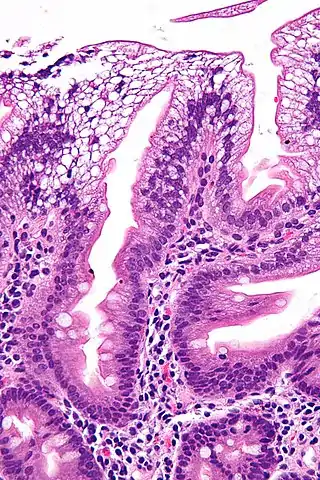

![]() Micrografía de una biopsia duodenal que muestra enterocitos con un citoplasma claro (debido a la acumulación de lípidos) característico de la abetalipoproteinemia. | ||